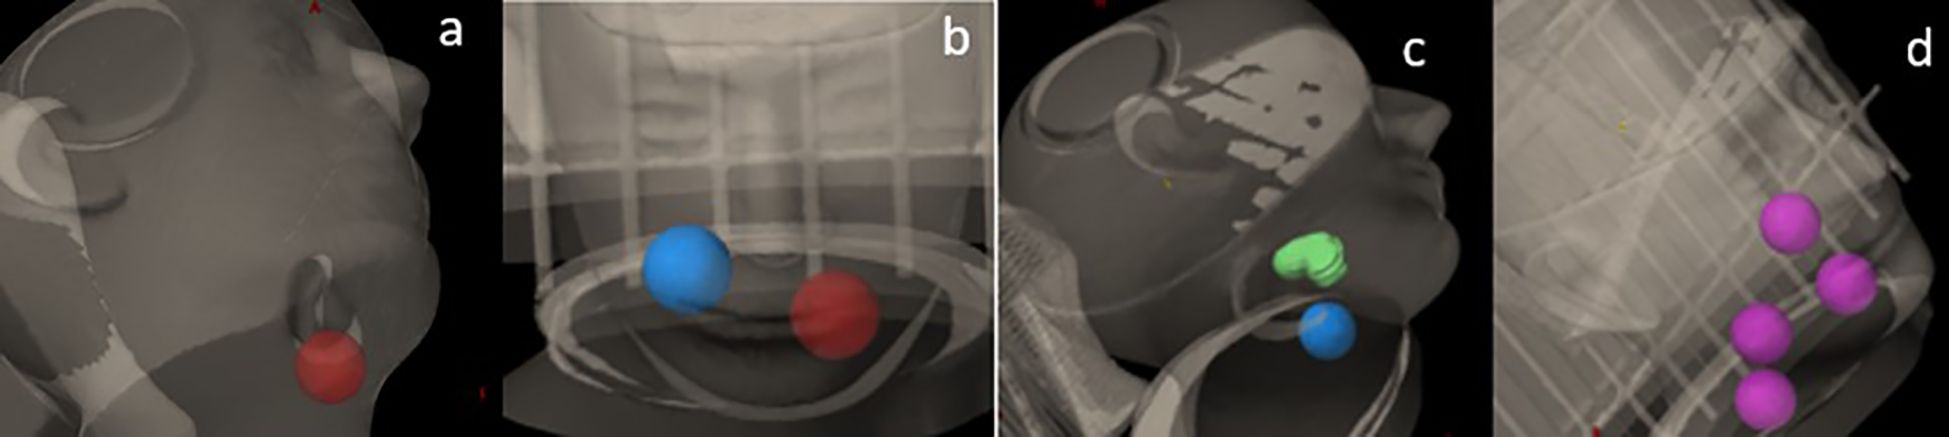

A Rando head phantom was scanned with a CT simulator using 120 kVp at 1-mm slice thickness. A series of SCART plans with one, two, and four targets were generated using Varian’s Eclipse (v15.6) treatment planning system (TPS). The plans were delivered using the TrueBeam STX with 120 HD MLC (Varian Inc., Palo Alto,CA, USA). The dosimetric parameters were then compared with the results from SCART plans reported by Massaccesi et al (16). As shown in Figure 1, sample cases included 1) one spherical target, 2) two spherical targets, 3) one spherical target and one irregularly shaped target, and 4) four spherical targets. Each spherical target was 3 cm in diameter (volume, 14.14 cm3). The irregularly shaped target was contoured with an effective volume of 14.1 cm3. There was a 6-cm center-to-center distance between two adjacent targets. However, in the sample case of four targets, two targets were deliberately placed with a center-to-center distance of 4 cm.

Figure 1. Sample cases with (a) one spherical target, (b) two spherical targets, (c) one spherical target and one irregularly shaped target, and (d) four spherical targets.